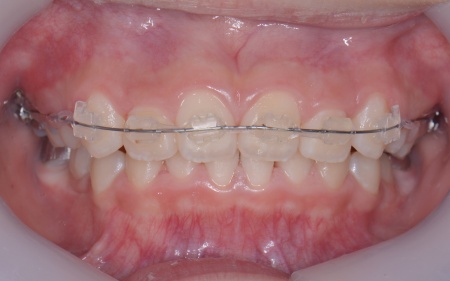

10歳女の子 成長期を利用した小児矯正治療で八重歯を改善した症例

「上前歯が八重歯になってきたのが気になる」とご相談いただきました。

拝見したところ、上の犬歯が歯列の外側に飛び出すように生えている、いわゆる八重歯でした。

さらに、上下の歯全体がデコボコに生えている「叢生(そうせい)」と呼ばれる状態で、これは歯が正しい位置に並ぶためのスペースが不足していることが原因だと考えられます。

次に歯の位置を整えるため、ワイヤー矯正を開始します。

上前歯6本と左右の奥歯の表面に「ブラケット」と呼ばれるボタン状の装置を設置し、そこにワイヤーを通して歯を少しずつ動かしていきました。

この装置は、歯の高さや位置のばらつきを整える「レベリング」を行うためのもので、拡大によって確保したスペースを活かしながら、歯並びを段階的に整えます。